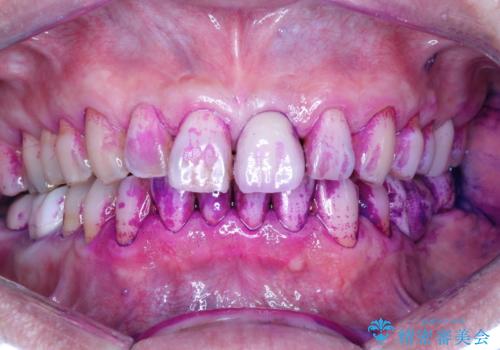

- 日頃の積み重なった茶渋・着色をエアフローにてクリーニングしました。

エアフローとは

エアフローはお水と強圧の風と細かいパウダーでお掃除していきます。

そのため、ブラシでは届きにくかった歯と歯の間の汚れをより落とすことが可能になります。